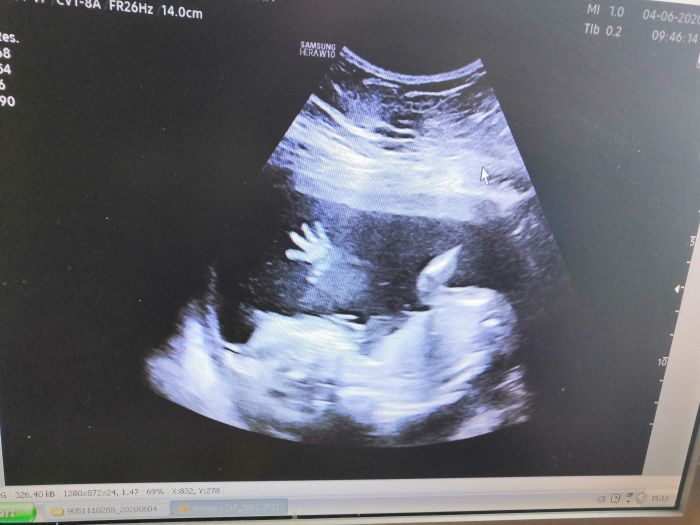

Ahojky holky, tak hlásím dnes kontrola ale jen taková rychlá. Moc vážení a rychlý ultrazvuk zda je vše v pořádku. Tak vše jde podle plánu. Za 4 týdny mě čeká druhý velký screening ve 21tt tak snad bude stále vše ok. Dokonce mi prcek zamával na rozloučenou.. Mám za sebou i kontrolu u obvodacky a EKG. To dopadlo také super. Jen mi dala nějaký prášky na otoky kdybych potřebovala.

Tak pohladte pupiky a mějte fajn večer...

Volavko, díky, přesně takové historky mi teď moc pomáhají :) Loli, ta fotka je úžasná, vzpomínka na celý život :)